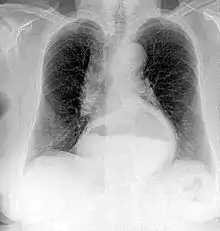

Projectional radiographs

Projectional radiography is the practice of producing two-dimensional images using X-ray radiation. Bones contain a high concentration of calcium, which, due to its relatively high atomic number, absorbs X-rays efficiently. This reduces the amount of X-rays reaching the detector in the shadow of the bones, making them clearly visible on the radiograph. The lungs and trapped gas also show up clearly because of lower absorption compared to tissue, while differences between tissue types are harder to see.

Projectional radiographs are useful in the detection of pathology of the skeletal system as well as for detecting some disease processes in soft tissue. Some notable examples are the very common chest X-ray, which can be used to identify lung diseases such as pneumonia, lung cancer, or pulmonary edema, and the abdominal x-ray, which can detect bowel (or intestinal) obstruction, free air (from visceral perforations), and free fluid (in ascites). X-rays may also be used to detect pathology such as gallstones (which are rarely radiopaque) or kidney stones which are often (but not always) visible. Traditional plain X-rays are less useful in the imaging of soft tissues such as the brain or muscle. One area where projectional radiographs are used extensively is in evaluating how an orthopedic implant, such as a knee, hip or shoulder replacement, is situated in the body with respect to the surrounding bone. This can be assessed in two dimensions from plain radiographs, or it can be assessed in three dimensions if a technique called '2D to 3D registration' is used. This technique purportedly negates projection errors associated with evaluating implant position from plain radiographs.[101]